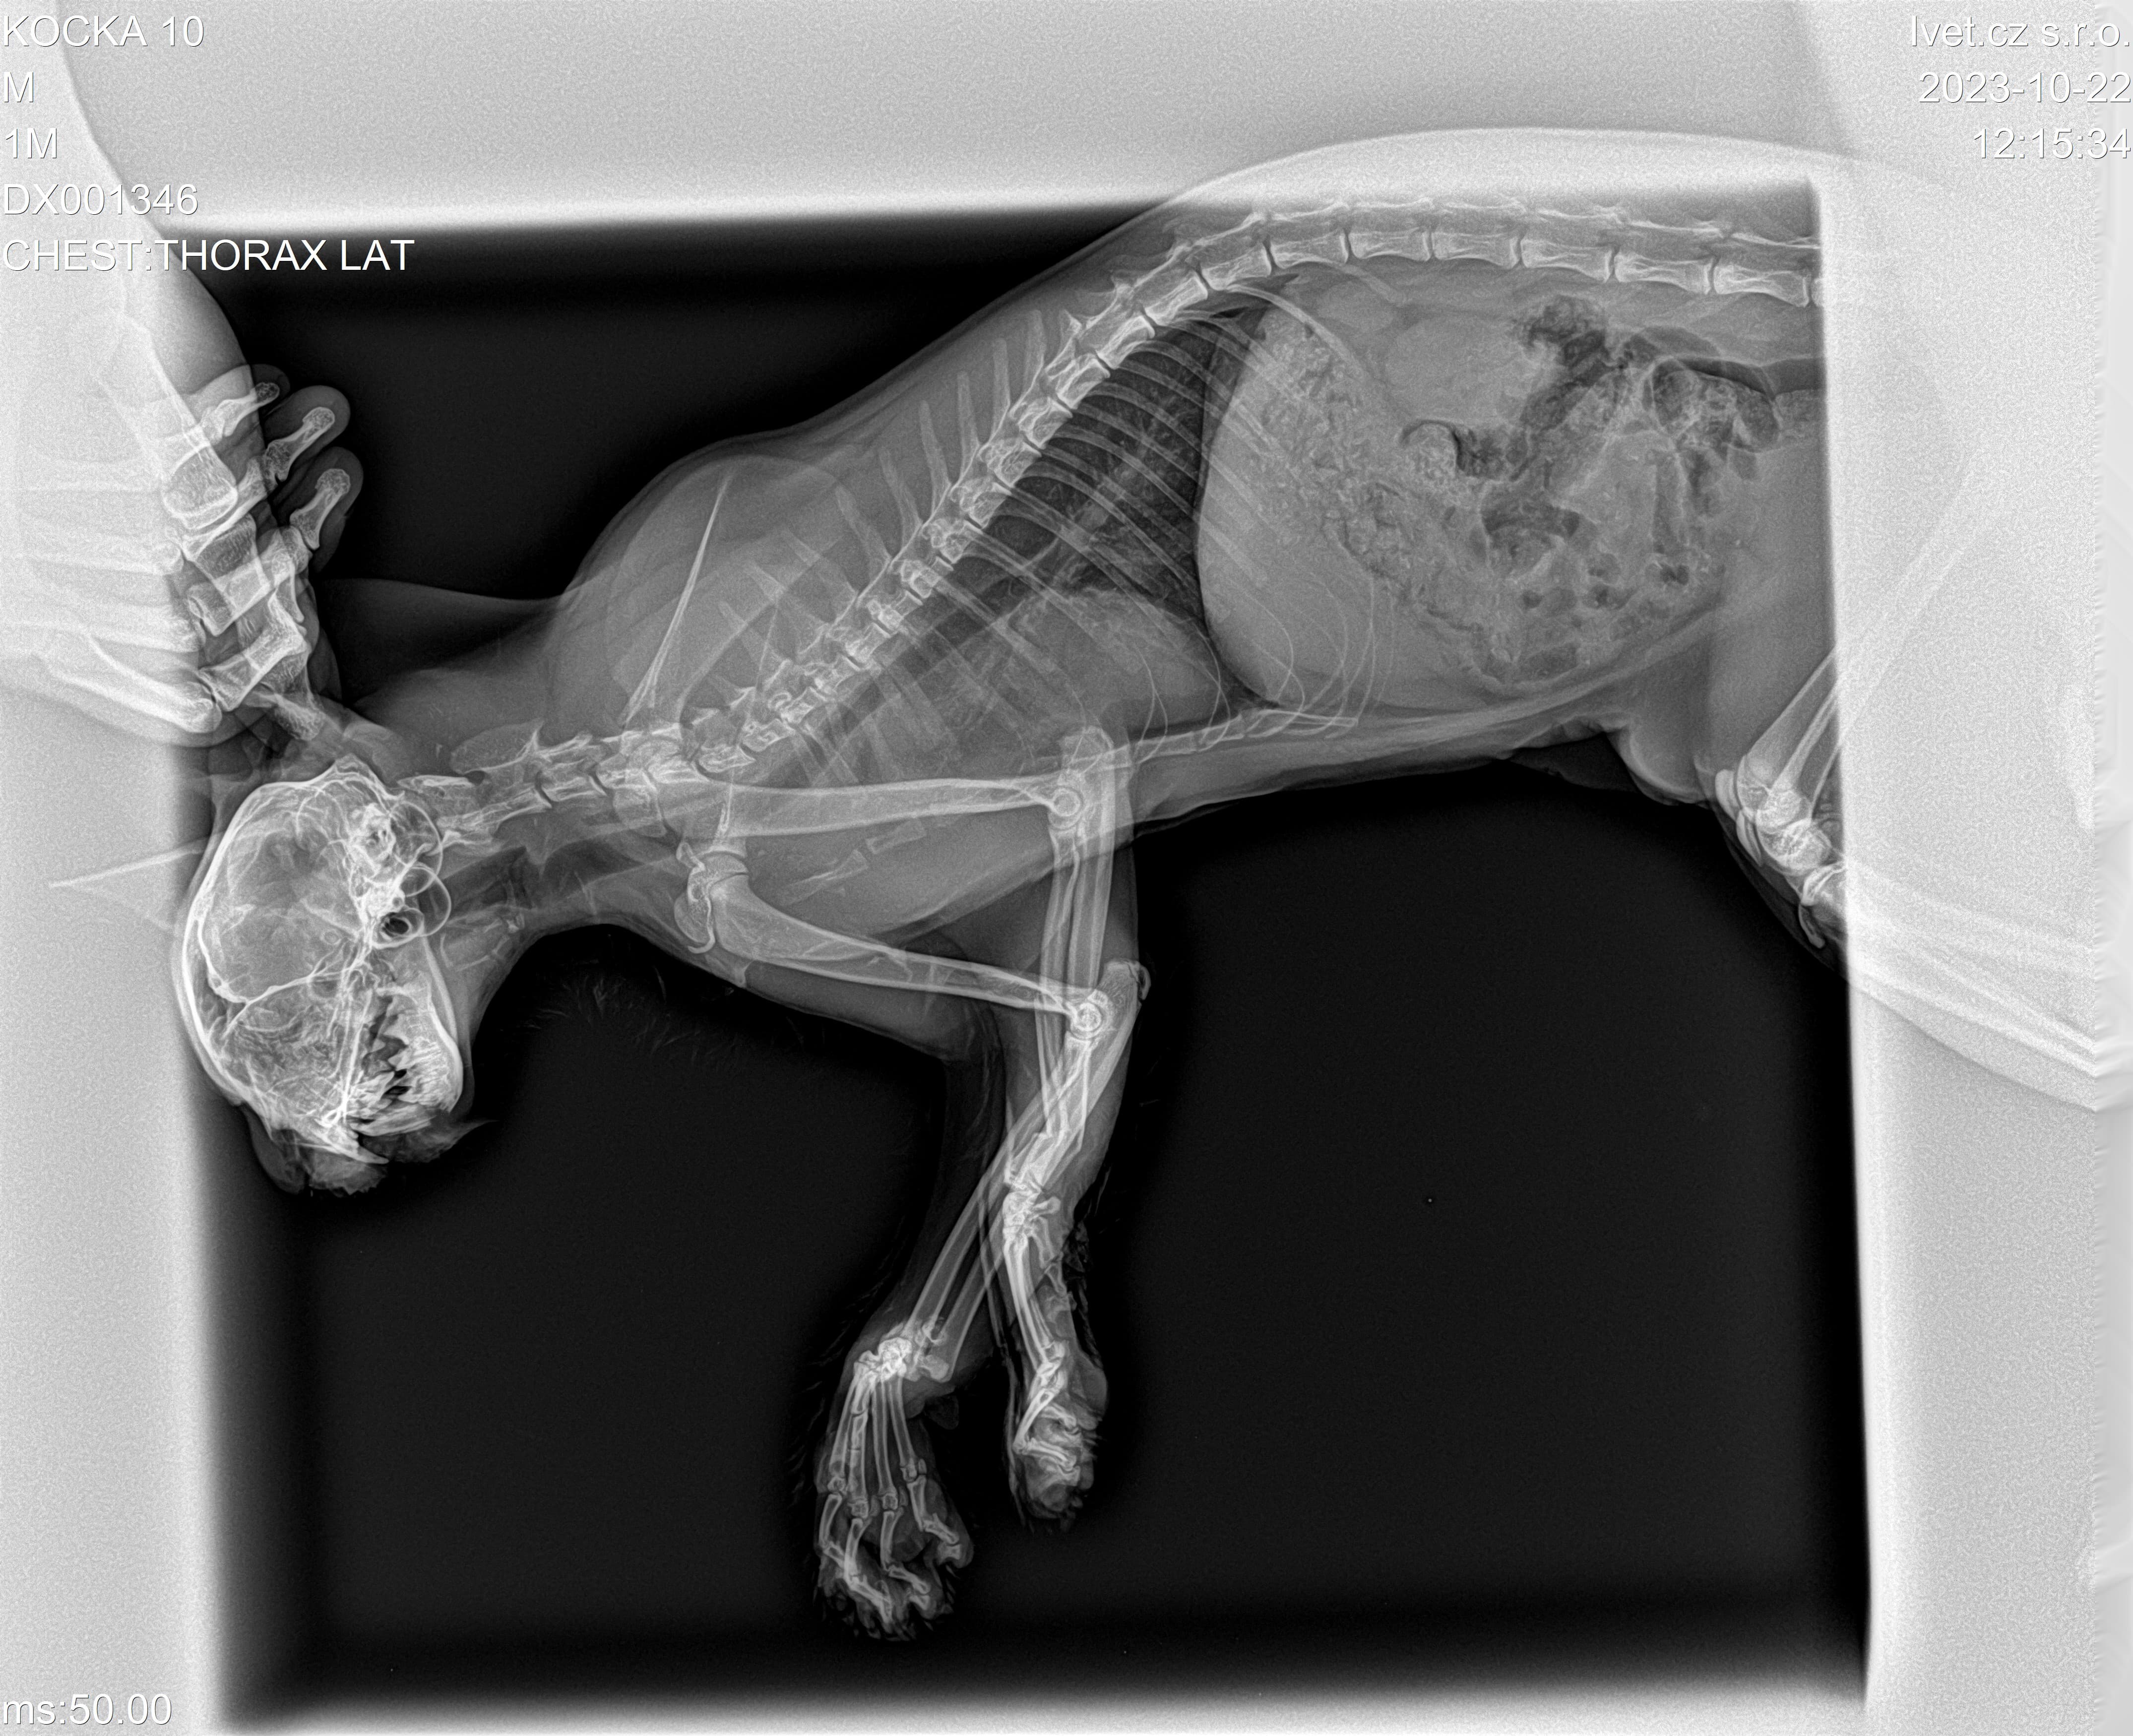

Jsem kočička Adélka a potřebuji vaši pomoc! Utekla jsem majitelce a srazilo mě auto.

Mám zlomené obě přední nožičky, a také mám zlomenou spodní čelist.